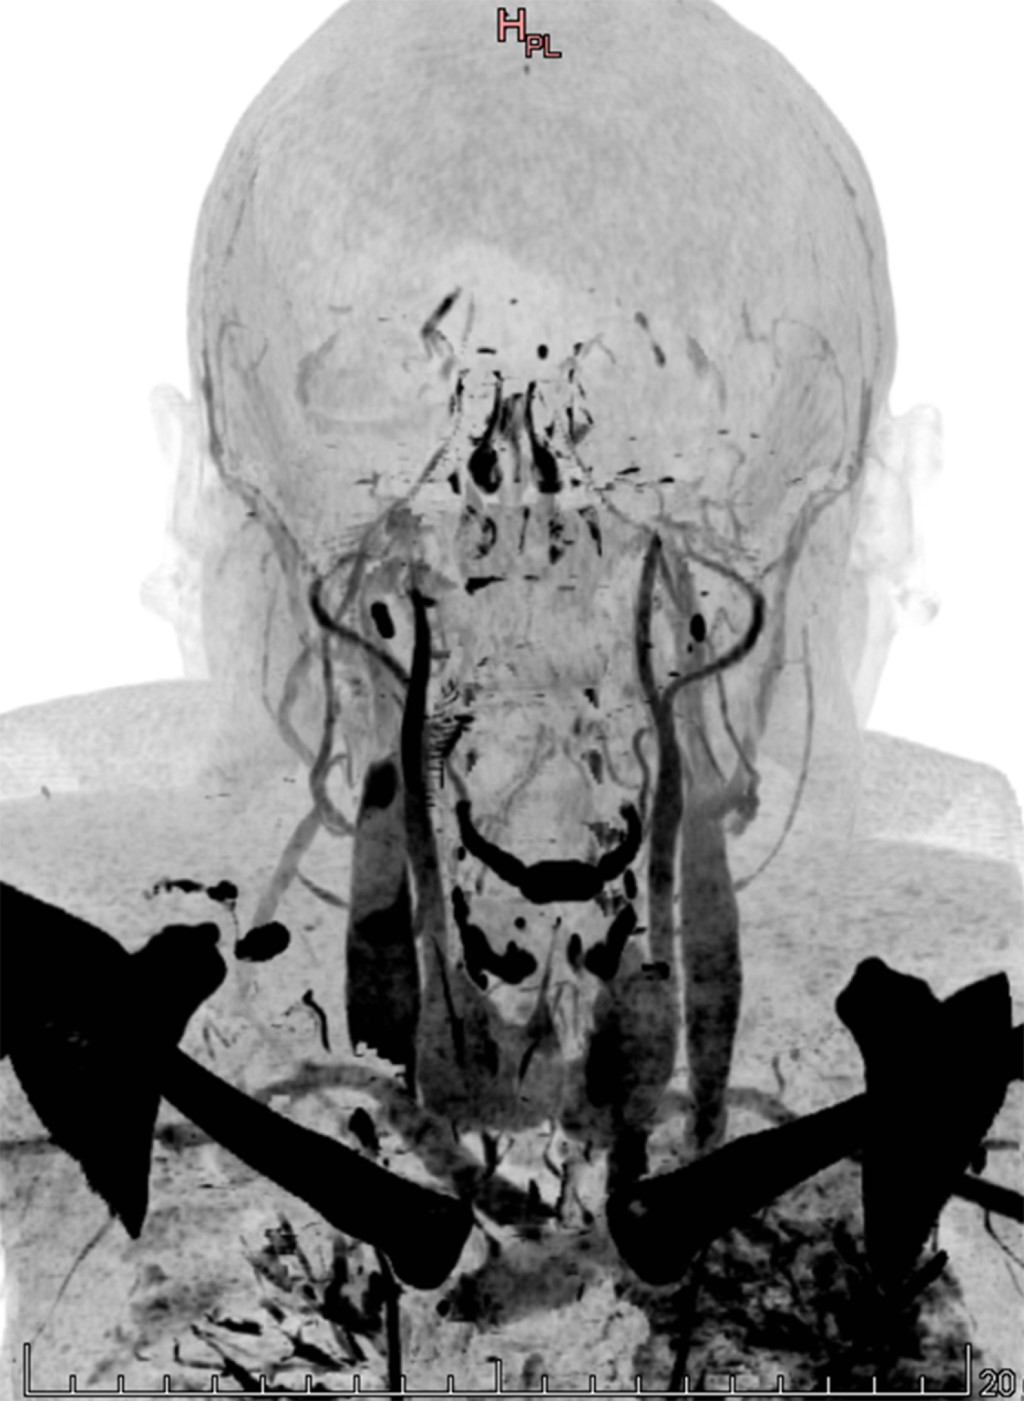

Figure 2